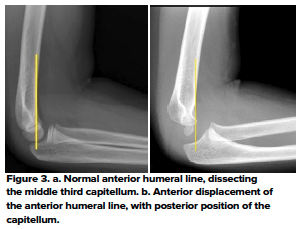

The anterior humeral and radiocapitellar lines are used to assess elbow alignment. The lines assess the geometric relationship of one bone to the other. Malalignment usually indicates fractures.

The anterior humeral line is drawn along the anterior cortex of the humerus and should bisect the middle third of the capitellum. Malalignment indicates a fracture - in most cases, posterior displacement of the capitellum in a supracondylar fracture. This sign relies on adequate ossification of the capitellum and therefore is reliable in children over the age of 4 years only.6 (Fig 3)